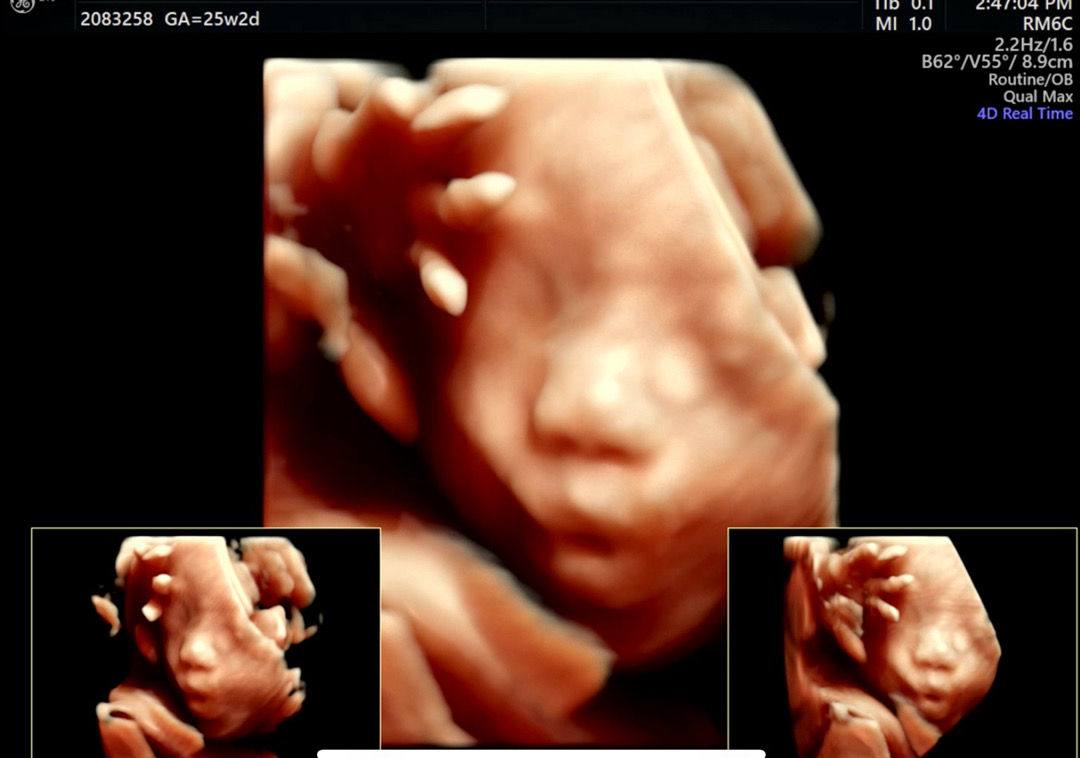

어제 25주 임당검사&입초보고 왔어요!

ㅎ ㅏ... 어제부로 도치맘 인정합니당 입초보는데 입꼬리가 내려가질 않더라구요❤️ (남편은 무려 눈물날 뻔 했다고ㅋㅋㅋㅋㅋㅋㅋㅋ) 아기도 너무 건강하고 임당도 114로 널널하게 통과,비타민D랑 철분수치까지 너무 좋다고 하셨어요! 기분 좋게 병원 다녀왔습니당ㅎㅎ 다음 진료까지는 4주에 한번 예약인데, 그 다음부터는 2주에 한번 내원하게 된다더라구요ㅎㅎ 점점 아가 만날 날이 가까워지는 듯 합니다~~☺️

아기가 협조를 잘 해주더라구욤 ㅎㅎ

손동작, 입모양 다 구엽😖

손가락으로 딱 포즈 취하네용ㅋㅋ너무 귀여워요